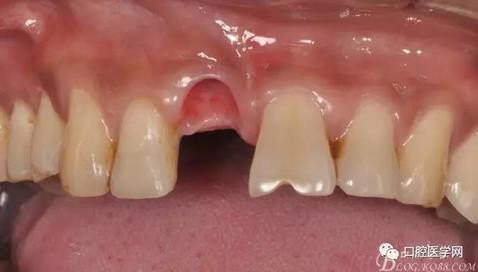

圖7 術(shù)后植入愈合基

圖8 術(shù)后即刻臨時(shí)冠修復(fù)